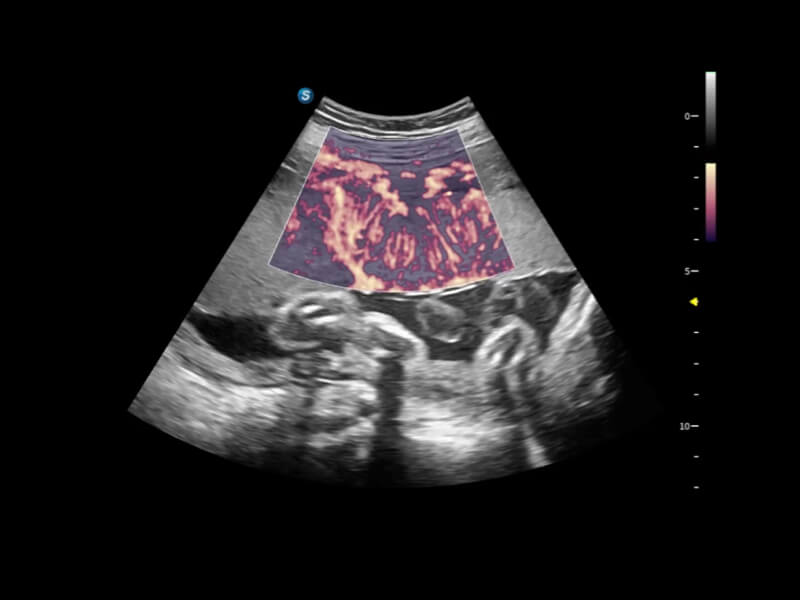

Exquisite Image Clarity & Hemodynamics

Image quality always lies at the core of definitive clinical outcomes. The P80 Elite introduces evolutional transducers with excellent 2D image clarity and color sensitivity for more confident assessment in anatomy and pathology.

Fine-tuned Hemodynamic Solution

A wide variety of hemodynamic diagnostic techniques enable effective blood flow signal detection across different scenarios.

FHR enables the observation of microvascular structure within organs with enhanced sensitivity and improved resolution, ensuring the precision in representing the actual state of blood circulation.

• Bright Flow

Bright Flow offers 3D-like color Doppler flow visualization without requiring a volume transducer, thereby strengthening the boundary definition of vessel walls.

• Micro F

Micro F efficiently distinguishes subtle blood flow signals from overlaying tissue motion, enabling heightened sensitivity and spatial resolution in hemodynamic depiction.